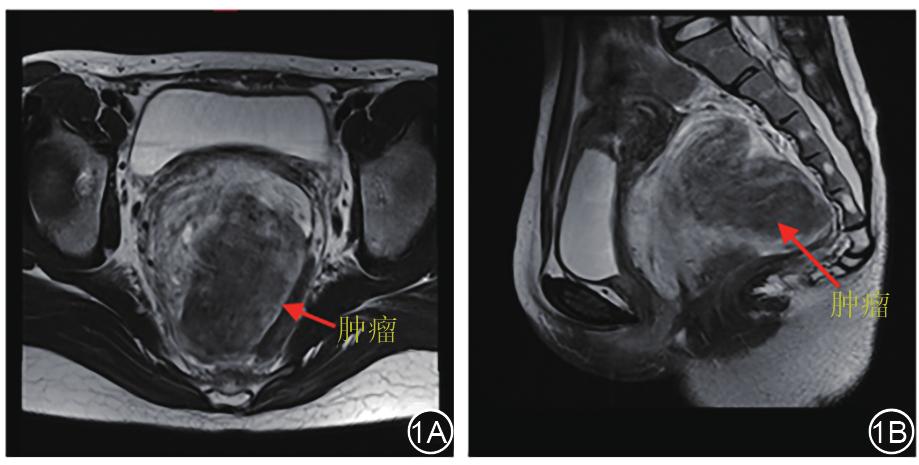

患者女性,19岁,BMI:19.0 kg/m 2 。因“排便困难1年”入院。查体:距肛缘2 cm,齿状线水平,膝胸位0~6点处巨大直肠壁外外压性肿物,质韧,活动度差,黏膜未见溃疡及占位。盆腔MRI:盆底阴道后方直肠左旁巨大肿物,边界尚清,信号不均匀,大小约9.2 cm×8.4 cm×9.9 cm,增强可见渐进性明显强化,推压子宫、宫颈、阴道及直肠,局部与直肠下段分界欠清(图 1A、图 1B)。影像学诊断:盆底阴道后方直肠左旁巨大肿物,倾向间叶组织来源,侵袭性血管黏液瘤(aggressive angiomyxoma, AA)可能,拟行腹腔镜盆腔肿瘤切除术。

图1 术前MRI显示肿瘤位于盆腔,与直肠关系密切。1A:轴位,1B:矢状位